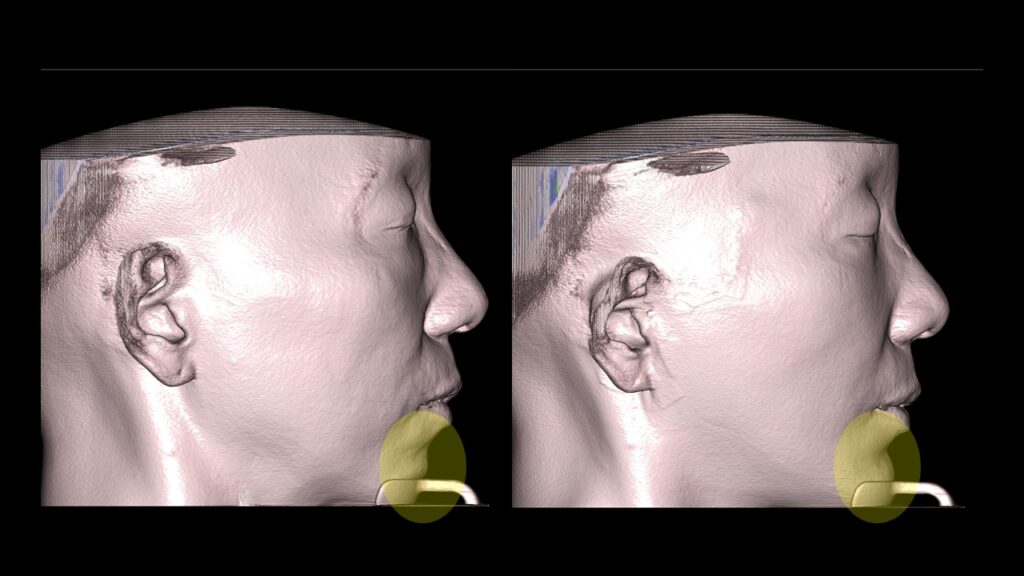

4. Case Studies (3DCT & Medical Photos)

-

Case 2: (Zygoma + Chin Advancement + Face Lift + Brow Lift) Dramatic improvement in the side profile and double chin within just 1 month.